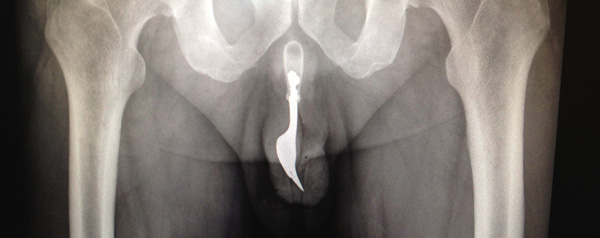

Vork in penis

Bij de foto linksboven: een 70-jarige Australiër kwam vorig jaar in het nieuws met een wel heel ongebruikelijk lichamelijk probleem. De heer in kwestie had een dessertvork – compleet met handvat én tanden – in zijn penis gestopt ‘ter seksuele bevrediging’. Hij kwam bloedend op de eerste hulp, waar het even duurde voor de artsen doorhadden wat de reden van zijn ‘stijve’ was. Met tangen en smeermiddelen verlosten zij

de man van de vork, en beschreven het geval in een wetenschappelijk tijdschrift. Opdat hun vakbroeders weten wat ze moeten doen met een volgende patiënt die wat al te speels is met zijn bestek.